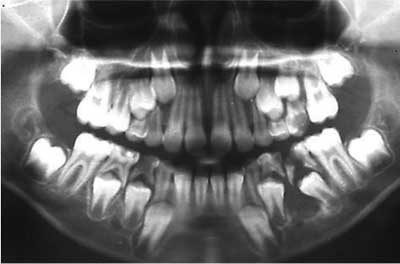

Foto 1: Rx pre 06-1999

Foto 1: Rx pre 09-1999